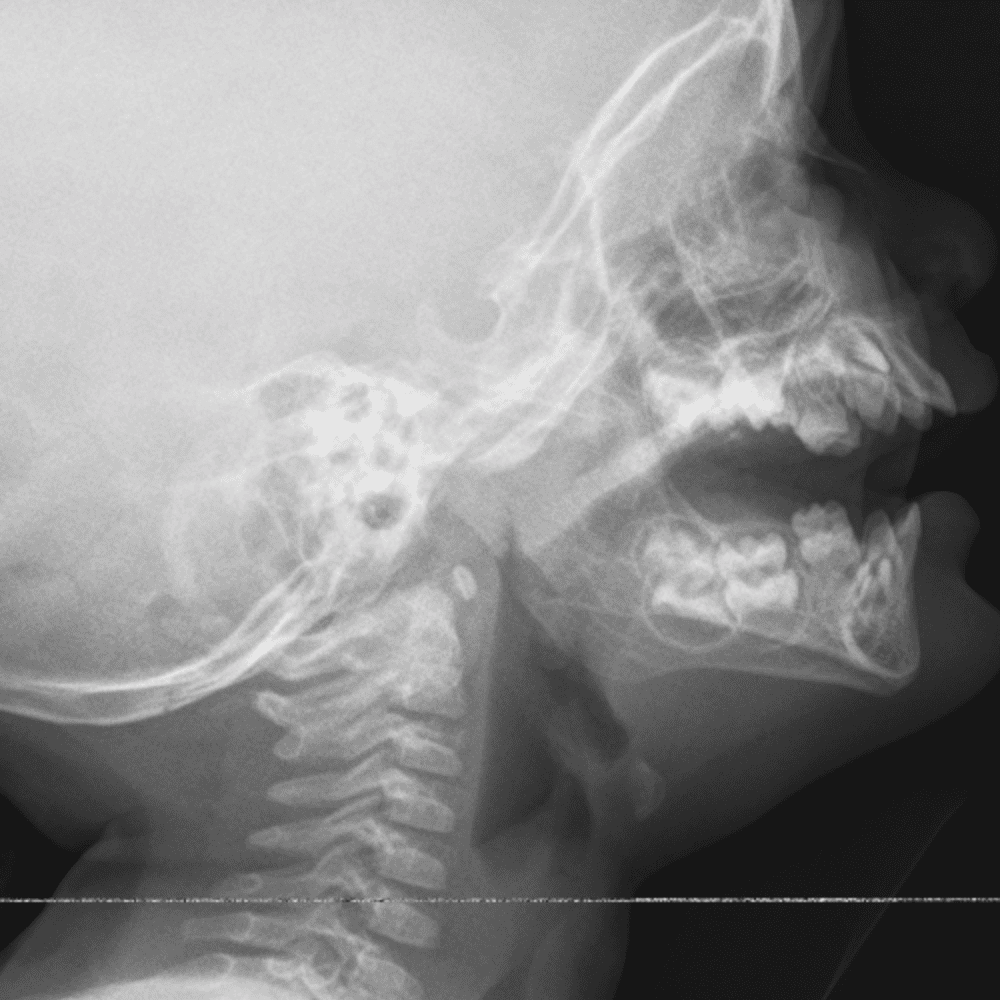

Peds Chest

Practice

Simulates call by including subtle or difficult cases and some normals.

50 cases